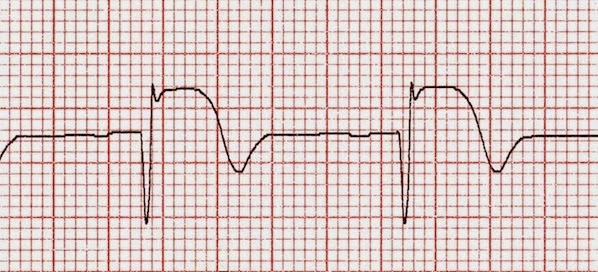

Duración óptima del tratamiento con beta bloqueadores después del infarto

El registro nacional francés muestra reducción de la mortalidad con el uso temprano de beta bloqueadores en el infarto agudo de miocardio, pero sin beneficio evidente de mantenerlo por más de un año. BMJ, 20 de septiembre de 2016